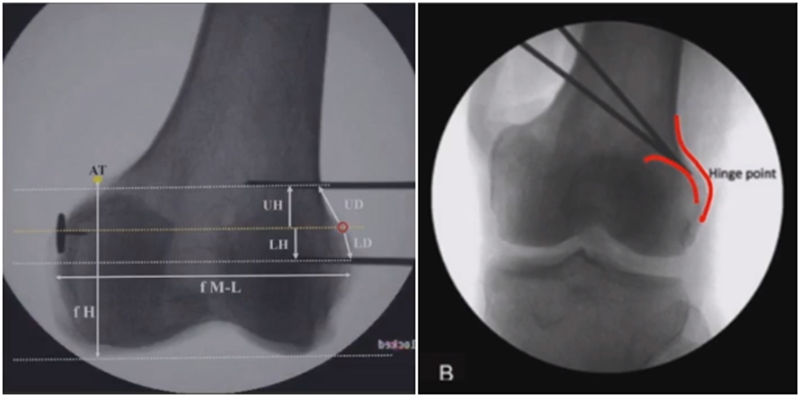

3、选择合页位置和截骨线

合页点的选择与HTO一样,通常需要尽可能接近畸形部位,既要有很好的骨质结构,还要有坚韧的软组织覆盖,以保证稳定性和术后有良好的血运。合页宽度不宜太长,通常保留在5mm。

合页点定位有两种方法,一种为定位在股骨外后髁上缘2mm位置,通常将此区域叫做“鹰嘴区”,以此为解剖标记法来定位合页点。

另一种通过导针从截骨入点向股骨外后髁后缘打出一条切线,此切线与外侧骨皮质的交点,也可作为合页点,这种方法称为导针法。这两种方法在手术之中是可以互为验证的。

合页点处于松质骨区,易形变区,如选择周边区域较脆易折断。另外合页点后方有小腿三头肌的附着点,有很好的的软组织和血运,综合来说作为合页非常合理。

合页点和截骨线已确定好,按照术前计划打入导针,测量截骨深度。